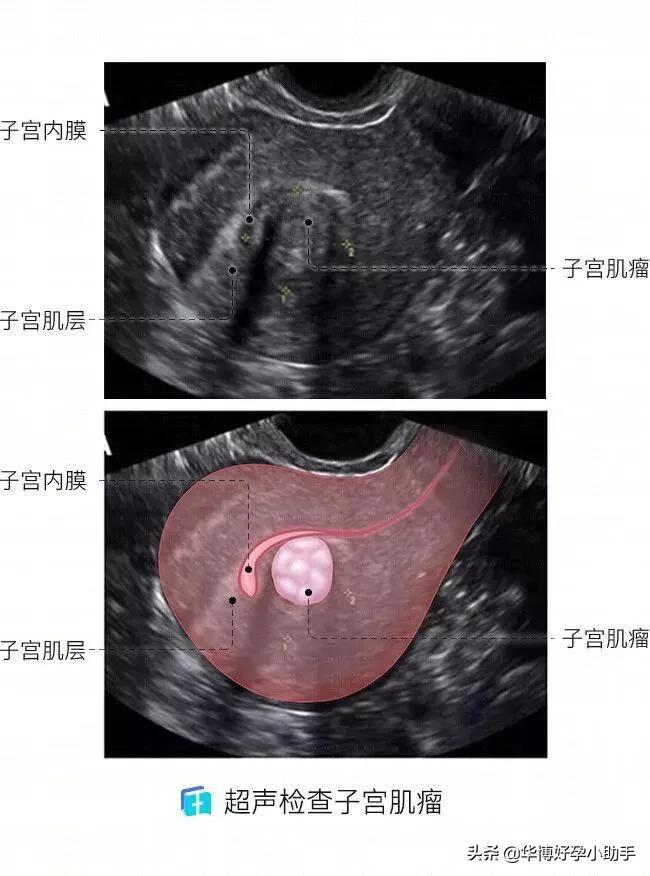

子宫肌瘤可以生长在子宫的任何位置,但不同位置的肌瘤发病率不同。

子宫壁就像是气球的外层,由外向内分为浆膜、肌层及黏膜(子宫内膜)三层。

肌瘤在每一层都可能生长:肌壁间肌瘤最常见,占60%~70%。浆膜下肌瘤约占20%。黏膜下肌瘤占10%~15%(见下图)。

多数肌瘤在B超等常规辅助检查下有相关声像的改变,较容易发现。